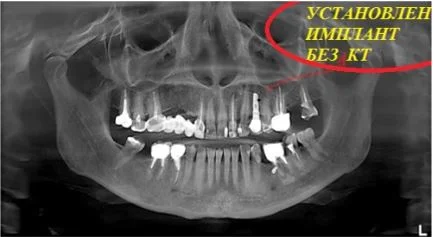

Давайте сравним снимки зубов, сделанные при помощи визиографа (слева), и при помощи компьютерной томографии (справа).

Как говорится, ощутите разницу. КТ - гораздо более точная и своевременная диагностика.

Компьютерная томография - это ключевой метод обследования в имплантологии

Воссоздавая орган (зуб) или даже совокупность органов, необходимо предельно точно знать исходную ситуацию. Корни зубов, каналы зубов, крупные сосудисто-нервные пучки, идущие внутри костной ткани, верхнечелюстная пазуха во всех подробностях и т.д. - в неискаженном виде все это можно увидеть только на компьютерной томограмме. Стоит ли говорить, что все эти структуры важны для имплантации, так как могут быть легко поврежденфы в ходе операции.